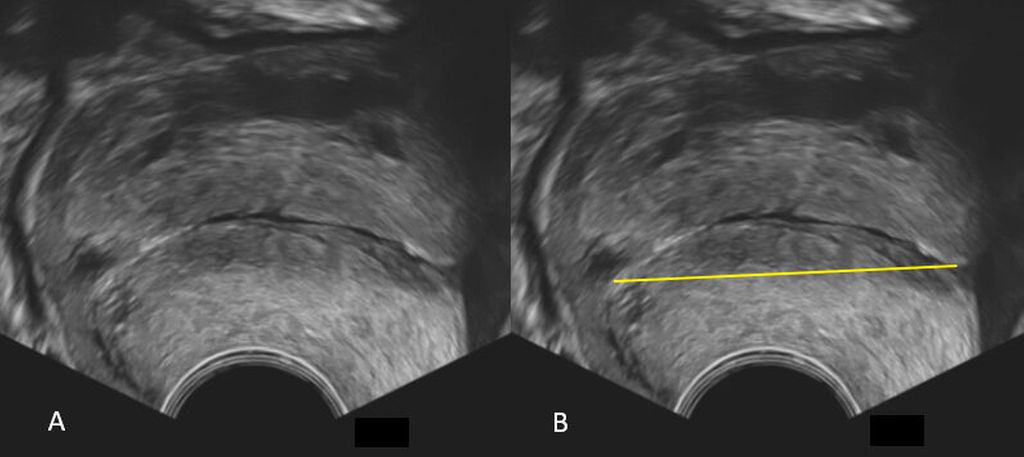

Der Zervikalkanal und die zervikale Mukosa müssen identifiziert werden.

Der Isthmus sollte nicht in die Messung der ZXL miteinbezogen werden. Hierzu eignet sich die Darstellung der hypoechogenen zervikalen Mukosa. Das Ende der Mukosa stellt den inneren MM dar. Der äussere MM ist der Punkt, an dem die vordere und hintere MM-Lippe zusammenkommen (Abb.1).

Korrekte Vergrösserung des Bildes

Zur genauen Darstellung der Zervixmorphologie und ihrer Strukturen hat das Bild 50 bis 75% des Bildschirms auszumachen (Abb.1).

Korrekte Platzierung der Messkreuze

Die Messung der ZXL erfolgt durch die Platzierung der Messkreuze am inneren und am äusseren MM. Gemessen wird in einer geraden Linie zwischen beiden Messpunkten und – trotz Krümmung der Zervix – nicht in zwei Segmenten. Die Zervix ist in 51% der Fälle bei einer Länge >25mm gekrümmt und immer gerade, wenn die ZXL <16mm beträgt. Insofern ist eine gerade Zervix immer verkürzt. Bei der Bildung eines Trichters wird das Messkreuz an die Spitze des Trichters gesetzt. Der Trichter selbst wird nicht gemessen (Abb.2).